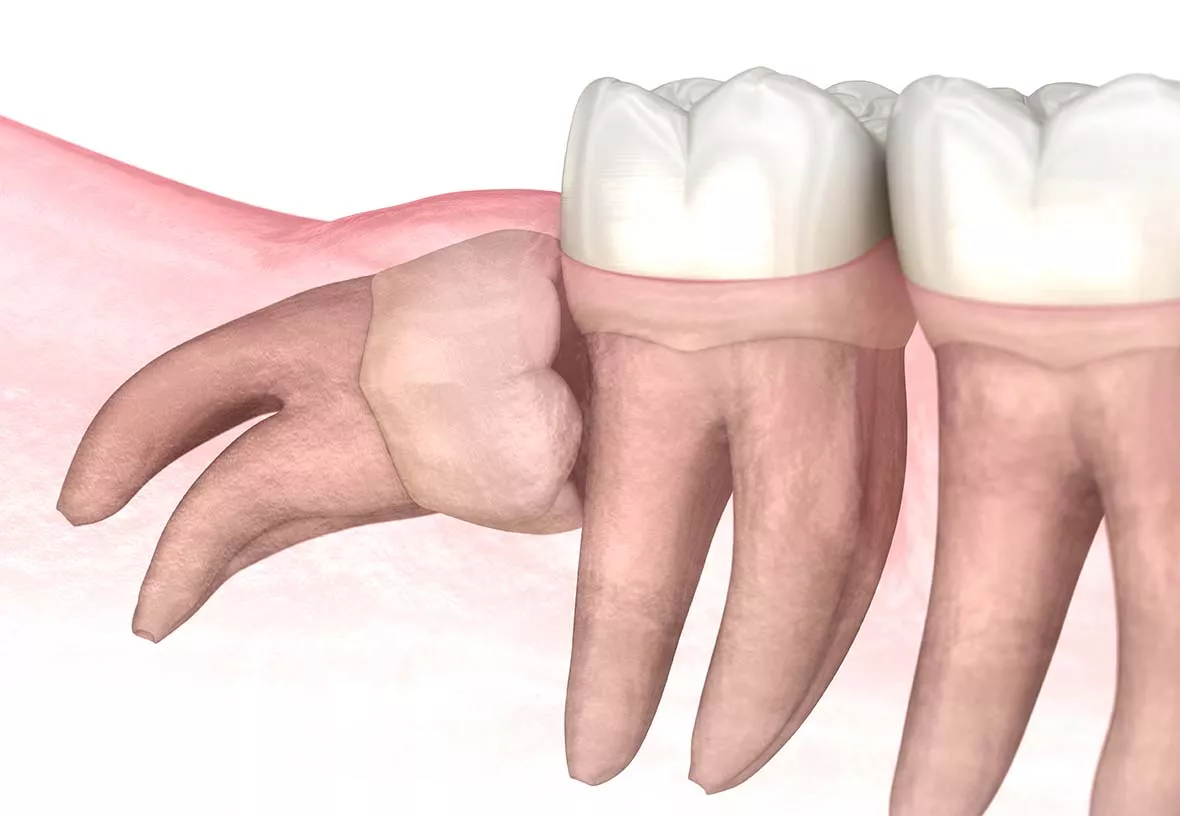

Your wisdom teeth are your last adult teeth. These large molars usually emerge behind your second set of molars at the back of your mouth. However, humans have evolved to have smaller jaws, and there is often not enough room in the jaw for the wisdom teeth to emerge correctly. When this happens, they can be crooked or grow under your other teeth and damage them. Your dentist will monitor the development of your wisdom teeth and recommend their extraction if they aren’t growing correctly.

The wisdom teeth are usually removed before they break through the gums. That means they need to be removed through surgery. Your dentist will make incisions near each tooth and then remove them. The treatment is done with a local anesthetic (freezing), and your dentist may also give you a mild sedative to help you stay relaxed during the procedure. After your wisdom teeth are removed, your dentist will usually close the incisions with sutures. You will usually be required to return to our office for a post-operative checkup to ensure you are healing as you should.